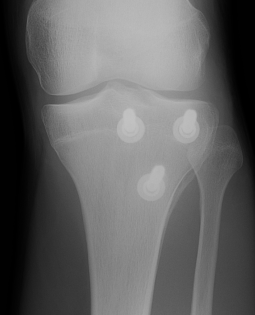

Type IB

Type IIB

Type III

Comminuted Type III